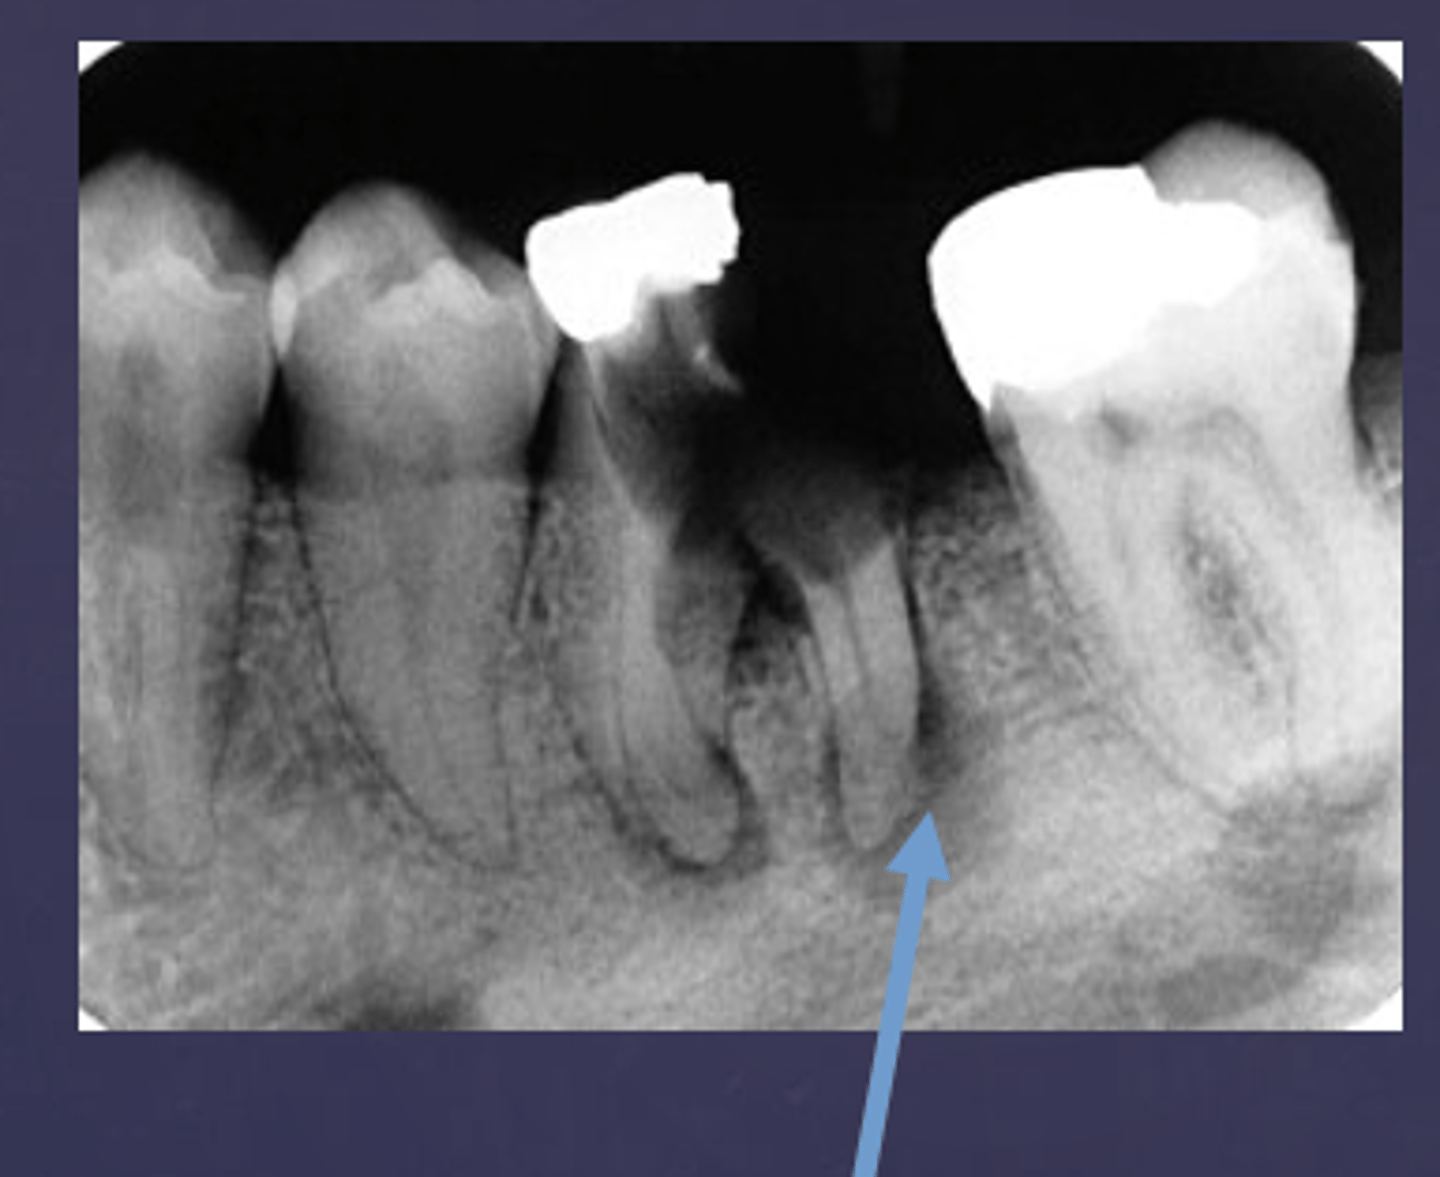

What are two defects that the arrows are pointing to?

- Widened PDL

- Sclerosis

The white arrow is showing what stage of lesion?

early (involving pulp, no changes in bone)

The blue arrow is showing what type of lesion?

chronic (loss of lamina dura, apical radiolucency and surrounding sclerotic bone reaction)